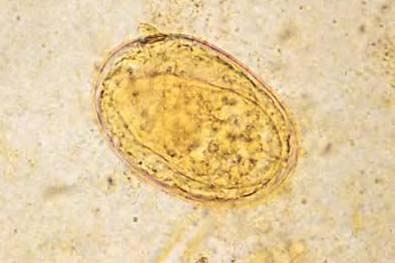

in human or ruminant stool

liver fibrosis, blacks disease for cows/sheep

history of eating raw aquatic plants

worldwide

Fasciola hepatica

egg

Fascioliasis

aquatic plant ingestion